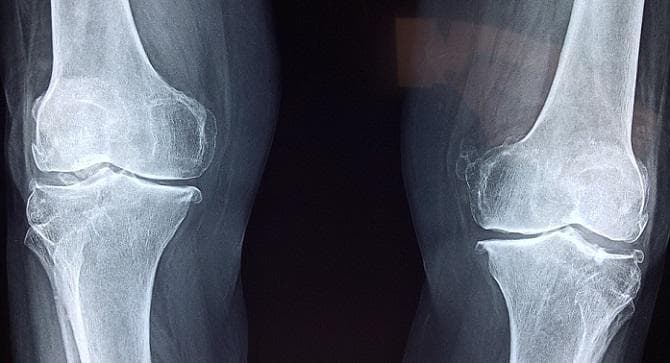

L’idea è innovativa perché colma una lacuna in campo medico: diagnosticare la predisposizione alla frattura ossea attraverso un algoritmo che in soli cinque minuti, grazie ad un complesso sistema matematico, analizza le radiografie.

Noi andiamo a studiare la struttura interna dell’osso: viene selezionata una regione e su di essa vengono simulati dei carichi: attraverso dei metodi matematici e l’analisi delle radiografie si ottiene un risultato che poi dal medico viene comunicato al paziente”.

Benchè questo sia un servizio software che viene in supporto ai medici, l’approccio è quello ingegneristico perché i modelli sono analoghi a quelli che studiano la resistenza di un aereo o di un’automobile di Formula 1: “Applichiamo lo stesso principio, attraverso un algoritmo personalizzato che in cinque minuti compreso l’upload della immagini radiografiche è in grado di fare tutto automaticamente”, prosegue.

“Si tratta quindi di un approccio assolutamente innovativo ed unico al mondo, completamente diverso da quello della densitometria perché la parte interna dell’osso sfugge alla normale analisi ma in realtà contribuisce in maniera importante alla resistenza dell’osso”.